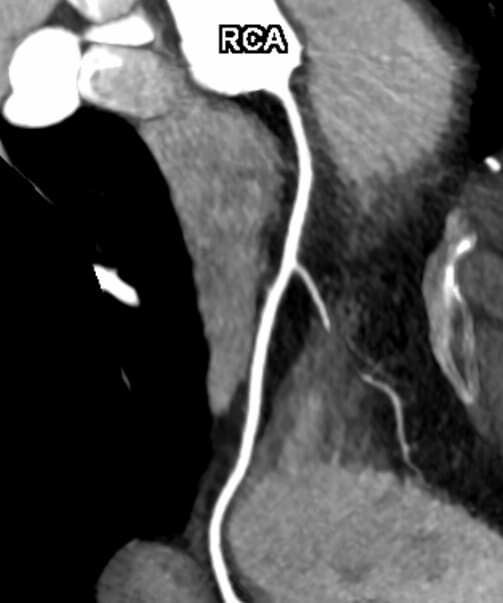

• Darstellung der Blutgefäße (sog. CT- Angiographie)

• Darstellung der großen Gefäße zur Erkennung von Gefäßverschlüssen (z. B. Mesenterial - Arterienembolie oder Einengungen von Gefäßen (z. B. Nierenarterien)

• Darstellung und Therapieplanung von Aneurysmen (CT- Angiographie)

• mehrdimensionale Darstellung vasculärer Strukturen mit zahlreichen Auswertungstools